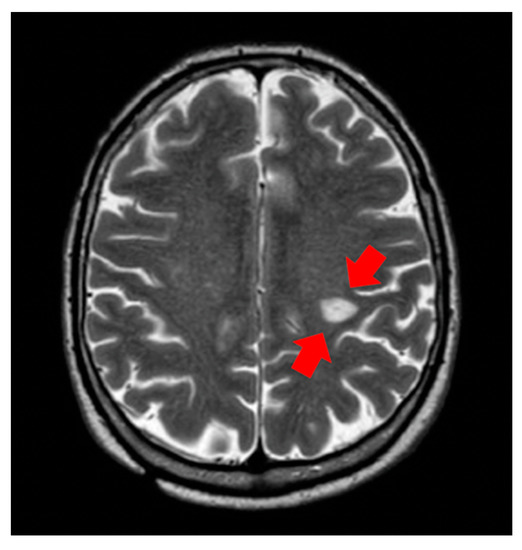

Encephalic Leukocytoclastic Vasculitis during Treatment with Sunitinib for Renal Cell Carcinoma: A Case Report

2. Cases and Methods